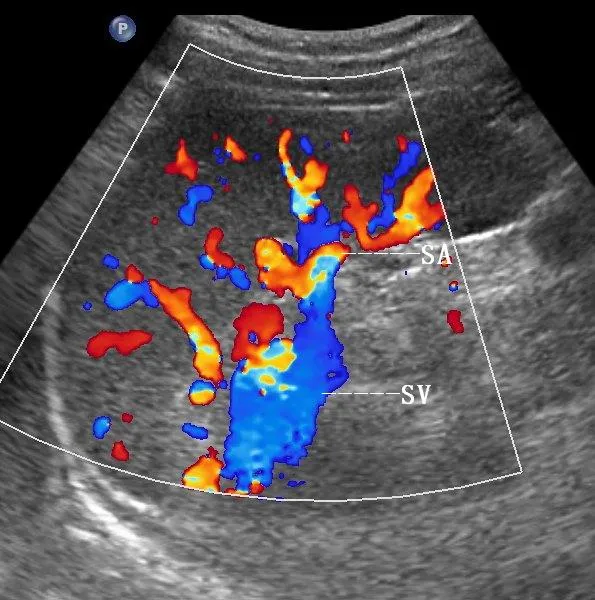

彩色多普勒,正常脾脏,显示脾门处红色的脾动脉(SA)和蓝色的脾静脉(SV) 。